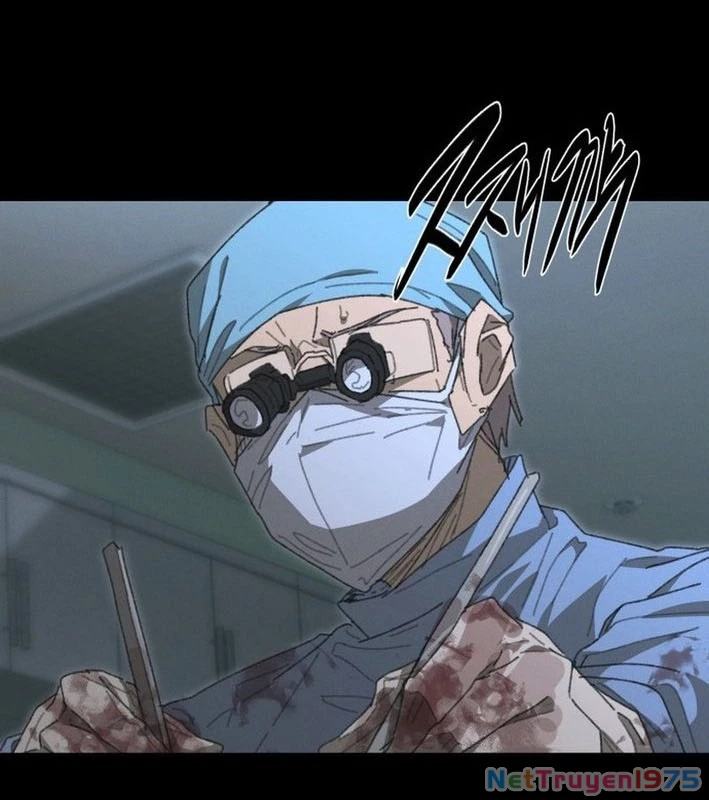

Kẻ Chôn Cất Quái Vật - Chapter 1